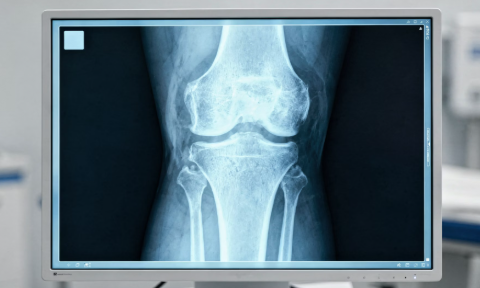

무릎 관절은 우리 몸에서 가장 많이 사용되는 관절 중 하나이기 때문에 작은 변화에도 소리가 발생할 수 있습니다.

무릎 관절에는 충격을 흡수하는 연골이 있습니다.

연골이 약해지거나 마찰이 증가하면 움직일 때 소리가 발생할 수 있습니다.

이 경우 나이가 들면서 더 흔하게 나타날 수 있습니다.